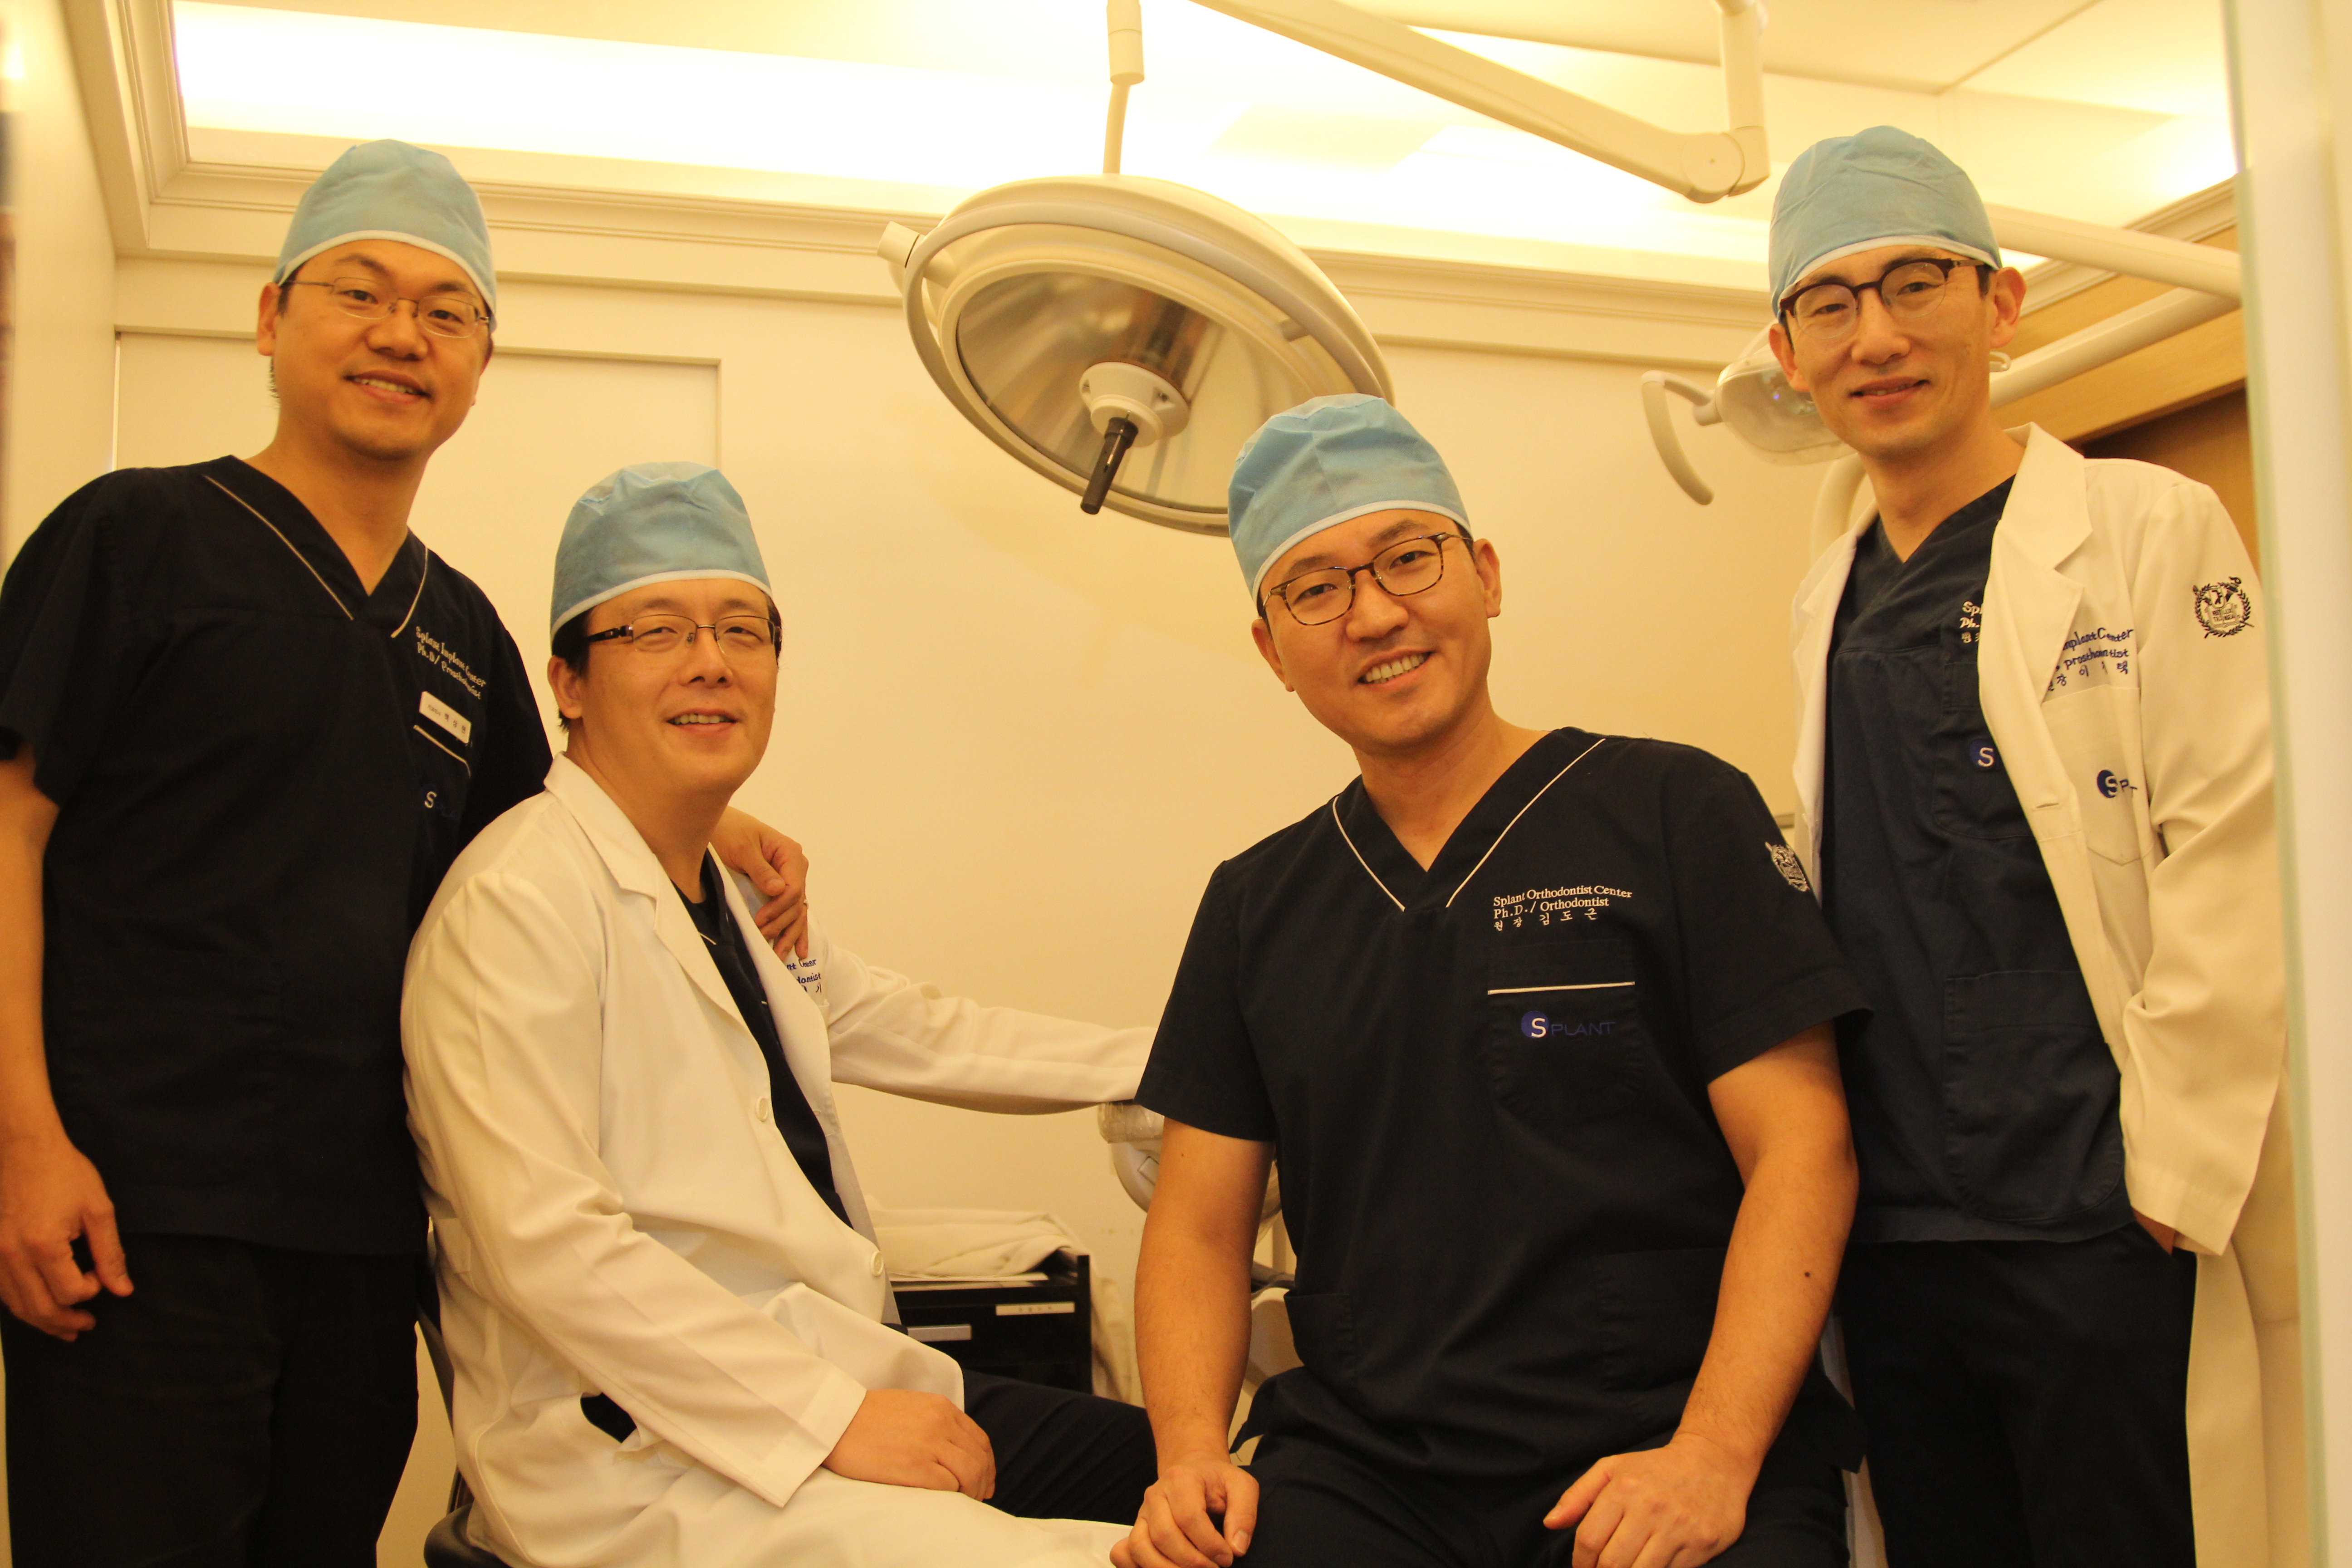

1. Лучшие специалисты

В нашей клинике в Отделении имплантации работают 4 стоматолога-ортопеда. Все они являются выпускниками Сеульского Национального Университета (№1 в Корее, входит в 30-ку лучших Университетов мира) и докторами медицинских наук. Многолетний опыт позволяется нашим врачам ставить точные более точные диагнозы и совершать более быстрое и качественное лечение.

В каждом отделении Стоматологическкой клиники Эсплант работают высококлассные специалисты-стоматологи, выпускники Сеульского Национального Университета, а также используется только самое современное оборудование. Если вы хотите получить качественное и надежное стоматологическое лечение, то приходите к нам!